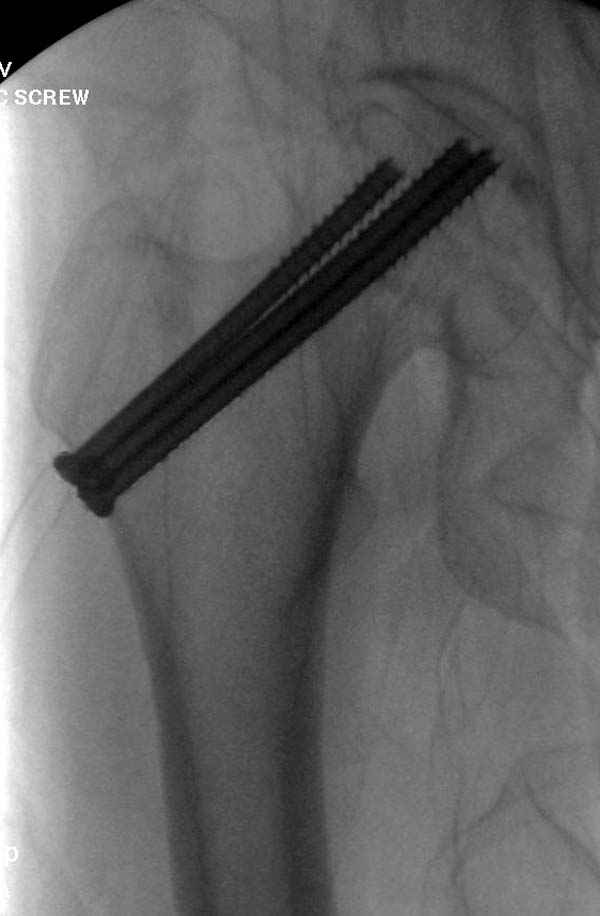

Re: неполный перелом шейки

Профилактику дальнейшего раскола неполного перелома шейки провели тремя канюлированными шурупами.

На второй день после выписки упал дома. Снимки приложены. Коллеги рекомендуют удаление шурупа и вытяжение. Что делать?